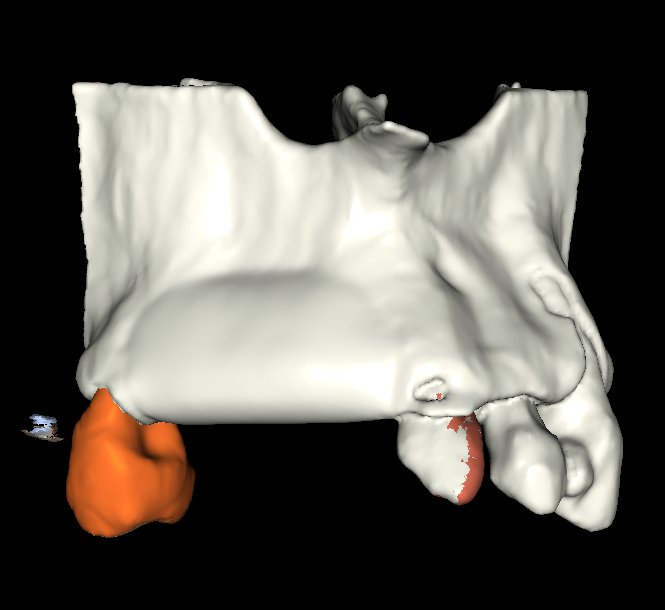

• Diagnóstico tomográfico (CBCT): lectura enfocada en regeneración ósea.

• Análisis del defecto óseo: tipo, morfología y severidad.

• BlueSkyPlan: diagnóstico, segmentación y análisis del defecto.

• Segmentación ósea y dental.

• Generación del defecto virtual.

• Control tridimensional del volumen a regenerar.